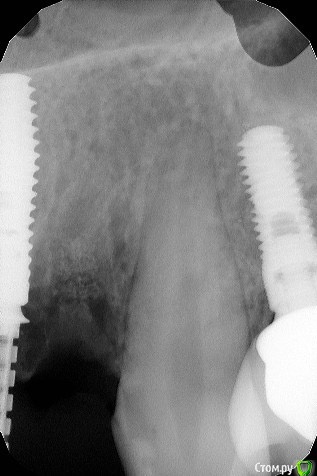

maksimstom Опубликовано 30 октября, 2020 Автор Поделиться Опубликовано 30 октября, 2020 27.10.2020 в 23:15, Irouil сказал: Покажите снимки, но, ИМХО, с таким дефектом ничего не получится скорее всего Кт после и прицелы области 1.2 и 2.2 Ссылка на комментарий

колесников Опубликовано 30 октября, 2020 Поделиться Опубликовано 30 октября, 2020 11,21 щит? Отлично! ,но нужно фланец делать и желательно имплант более небно. 22 следовало консервацию лунки сделать,теперь надо спасать 21,22,23 Ссылка на комментарий

maksimstom Опубликовано 30 октября, 2020 Автор Поделиться Опубликовано 30 октября, 2020 11,21 щит? Отлично! ,но нужно фланец делать и желательно имплант более небно. 22 следовало консервацию лунки сделать,теперь надо спасать 21,22,23 щита нет, ксено там. Консервировал 22, на прицеле с Графтом это 22. Фланец сдт? Ссылка на комментарий